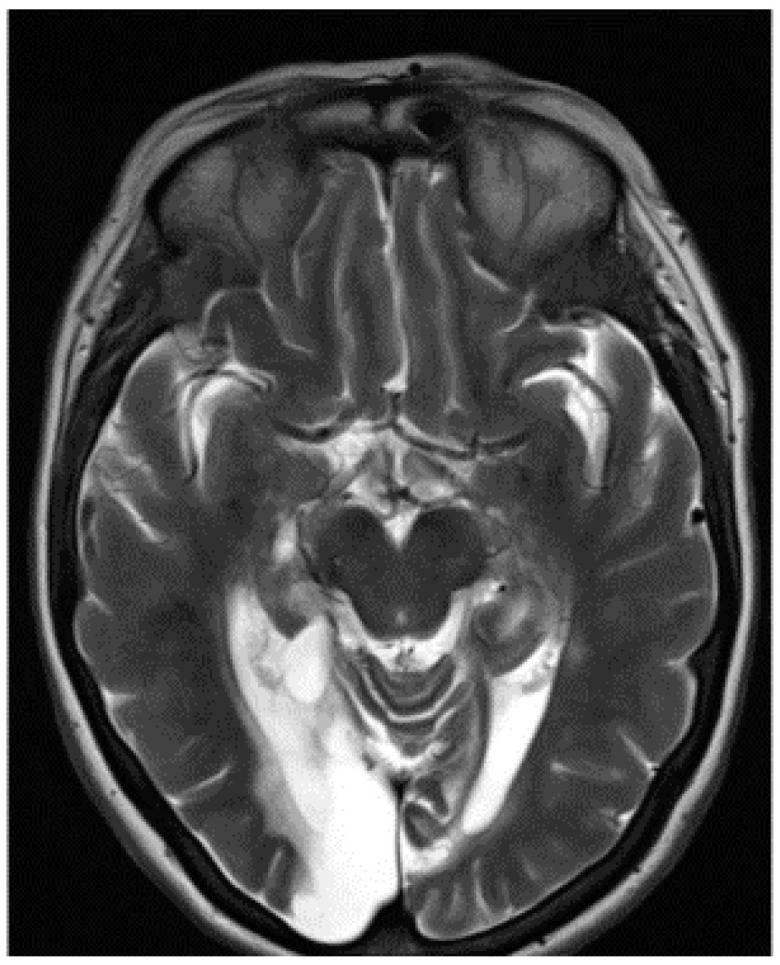

Methods: The patient received a neuropsychological assessment and underwent CT and MRI. Eye movements were recorded during the following tasks: (1) famous face identification, (2) facial emotion recognition, (3) identification of Ishihara colour plates, and (4) identification of both local and global letters in Navon composite letters, presented either alone or surrounded by filled black circles, which we hypothesised would impair global processing by disrupting fixation.